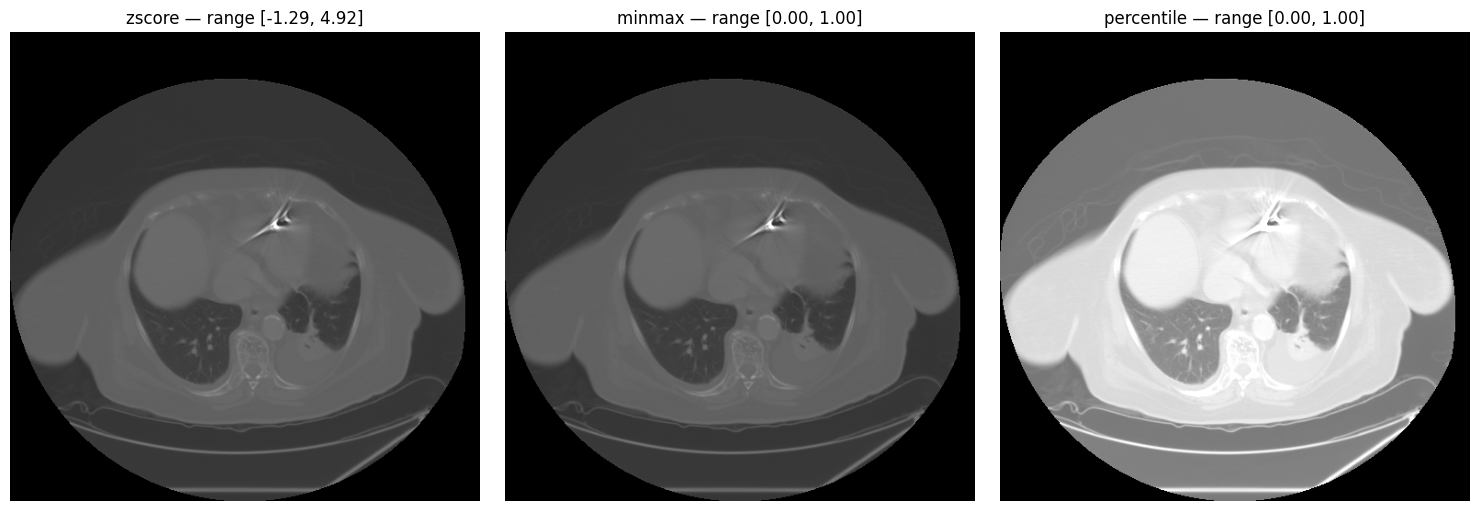

Intensity Normalization

Three normalization methods are available: z-score, min-max, and percentile.

normalization.py

methods = ["zscore", "minmax", "percentile"]

norm_slice = image[SLICE_HEART]

fig, axes = plt.subplots(1, 3, figsize=(15, 5))

for ax, method in zip(axes, methods):

normalized = processor.normalize_intensity(norm_slice, method=method)

ax.imshow(normalized, cmap="gray")

ax.set_title(f"{method} — range [{normalized.min():.2f}, {normalized.max():.2f}]")

ax.axis("off")

Z-score, min-max, and percentile normalization comparison